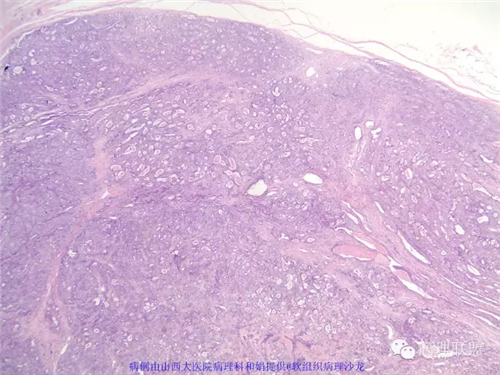

M,57岁,右膝关节外侧皮下肿物10余年,活动度好。

本例形态学上是非常典型的双相型滑膜肉瘤,滑膜肉瘤临床上大部分表现为生长缓慢的肿瘤。以青壮年多见,主要发生于四肢大关节附近,也可见于其他少见部位,如肺、肾等实质器官,形态学分为5种类型:单相纤维型、单相上皮型、双相型、低分化梭形细胞型和小细胞型。有文献报道个别患者有长达20年的病史。